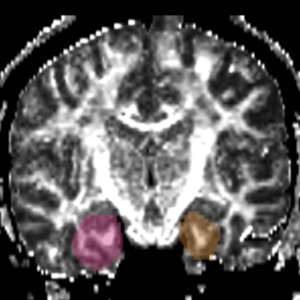

Arcuate Fasciculus

Connects Broca’s and Wernicke’s areas. Involved in language processing. Abnormalities here could be related to thought disorder and semantic processing disruptions that are hallmarks of schizophrenia.

These labelmaps ('caseD00XXX-FS-arcuate-final.nhdr') were created using automatic gray matter parcellation in Freesurfer and coregistered in Slicer to corresponding DTI dataset. The labelmaps were dilated in Slicer to increase coverage of gray matter.

Figure 12. Gray matter ROI's for Arcuate Fasciculus tractography

Figure 13. Gray matter ROIs (right side) in 3D

The color coding of the resulting ROIs is as follows:

ROI 1: Superior Temporal Gyrus - Left(5) - Right(6)

ROI 2:Inferior Frontal Gyrus- Left(13) - Right (14)